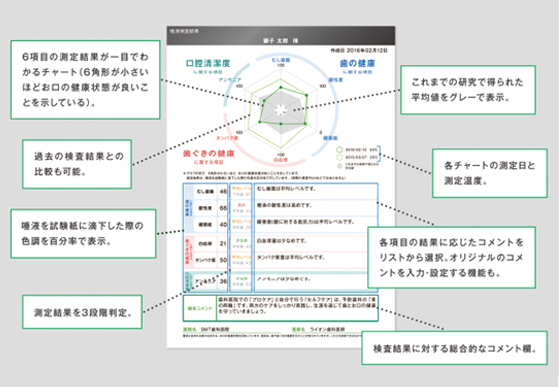

唾液検査Saliva

唾液検査でむし歯や歯周病のリスクがわかるという事をご存知ですか?

採取した唾液で<むし歯菌・酸性度・緩衝能・白血球・タンパク質・アンモニア>

の6項目を測定・分析し、今の口腔内環境を確認することができます。

この結果を活かし、治療やメンテナンス、自宅でのセルフケアをもっと充実させることができます。

の6項目を測定・分析し、今の口腔内環境を確認することができます。

この結果を活かし、治療やメンテナンス、自宅でのセルフケアをもっと充実させることができます。

検査はとても簡単!

①洗口液をお口に含む

②10秒間ゆすぐ

③紙コップに吐き出す

あとは結果が出るまで5分程度待つだけです!

検査結果は患者様にも大変理解しやすいグラフになっています。

- むし歯や歯周病は大丈夫かな?と心配な方

- 自分に合ったメンテナンスを受けたい方

- 自分に合ったデンタルグッズを使いたい方

- 今のお口の中の状態を知りたい方

1回1,000円(税別・保険適用外)で行なっておりますので、ご予約の際にお申し付けください。